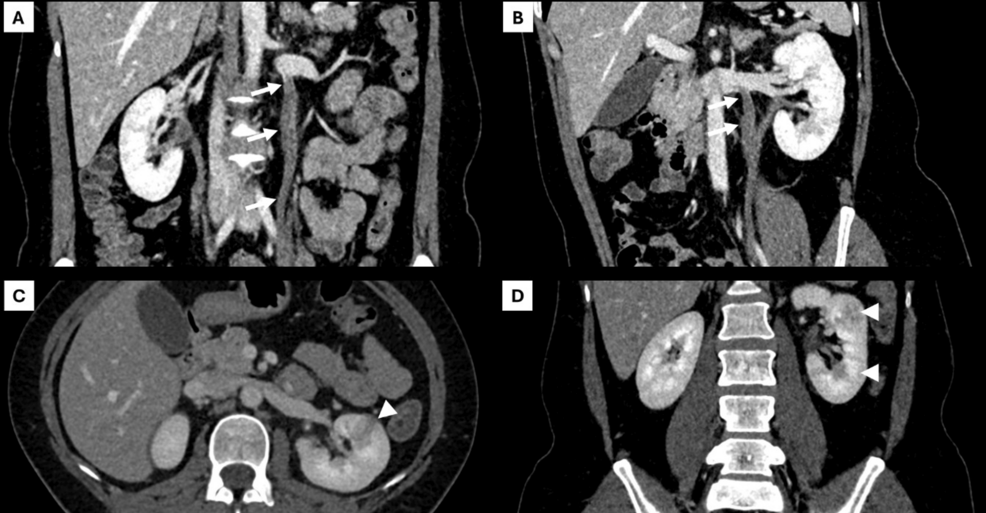

#急性腎盂腎炎に伴う非産科性卵巣静脈血栓症が救急外来を受診した1例